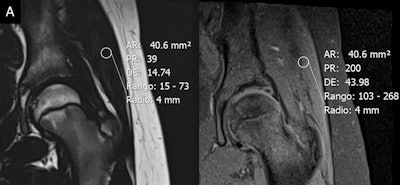

In addition, T2-mapping sequences, previously used for assessing cartilage damage, may be applied for evaluation of fatty infiltration and edema in patients with sarcopenia, they explained.